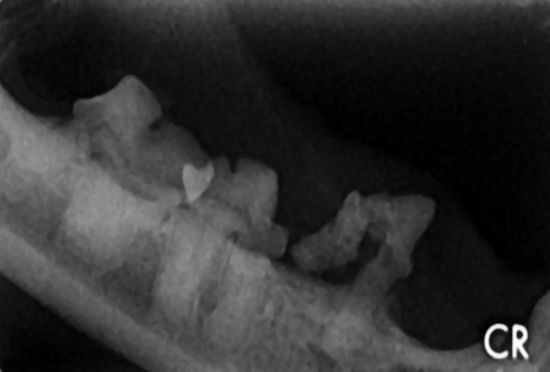

Digitales Dentalröntgen bei Hund, Katze und Heimtier

Viele schmerzhafte Erkrankungen, die nur von undeutlichen Krankheitssymptomen wie Gewichtsverlust, geringere Futteraufnahme, Zurückgezogenheit durch chronische Schmerzen begleitet werden, haben ihren Ursprung in der Maulhöhle.

Beim Heimtier kennen wir die Problematik mit den lebenslang wachsenden Zähnen, kleine Fehlstellungen und Wurzelerkrankungen können hier zur vollständigen Futterverweigerung führen.

Bei Katzen sehen wir manchmal einen entzündeten Zahnfleischsaum, eine Gingivitis, manchmal fällt den Besitzern auch auf, dass ihr Tier nur einseitig kaut oder bei der Futteraufnahme das Futter wieder herausfallen lässt. Dies sind Anzeichen für Schmerzen!

Schaut man ins Katzenmaul wirkt alles auf den ersten Blick normal, doch das ist trügerisch.

65 % der Zahnerkrankungen bei der Katze finden unterhalb des Zahnfleischsaumes an der Zahnwurzel und im Kieferknochen statt, 40 % davon lassen sich nur durch Röntgenaufnahmen finden.

Hier kann nur das dentale Röntgen, so wie wir es von unserem Zahnarzt helfen, die erkrankten Zähne zu identifizieren.

Unsere digitale Dentalröntgeneinheit hilft uns schnell und zuverlässig die erkrankten Zähne zu erkennen und zu therapieren, so können wir die Diagnose durch das Dentalröntgen und die Therapie innerhalb einer einzigen Narkose durchführen........mehr...